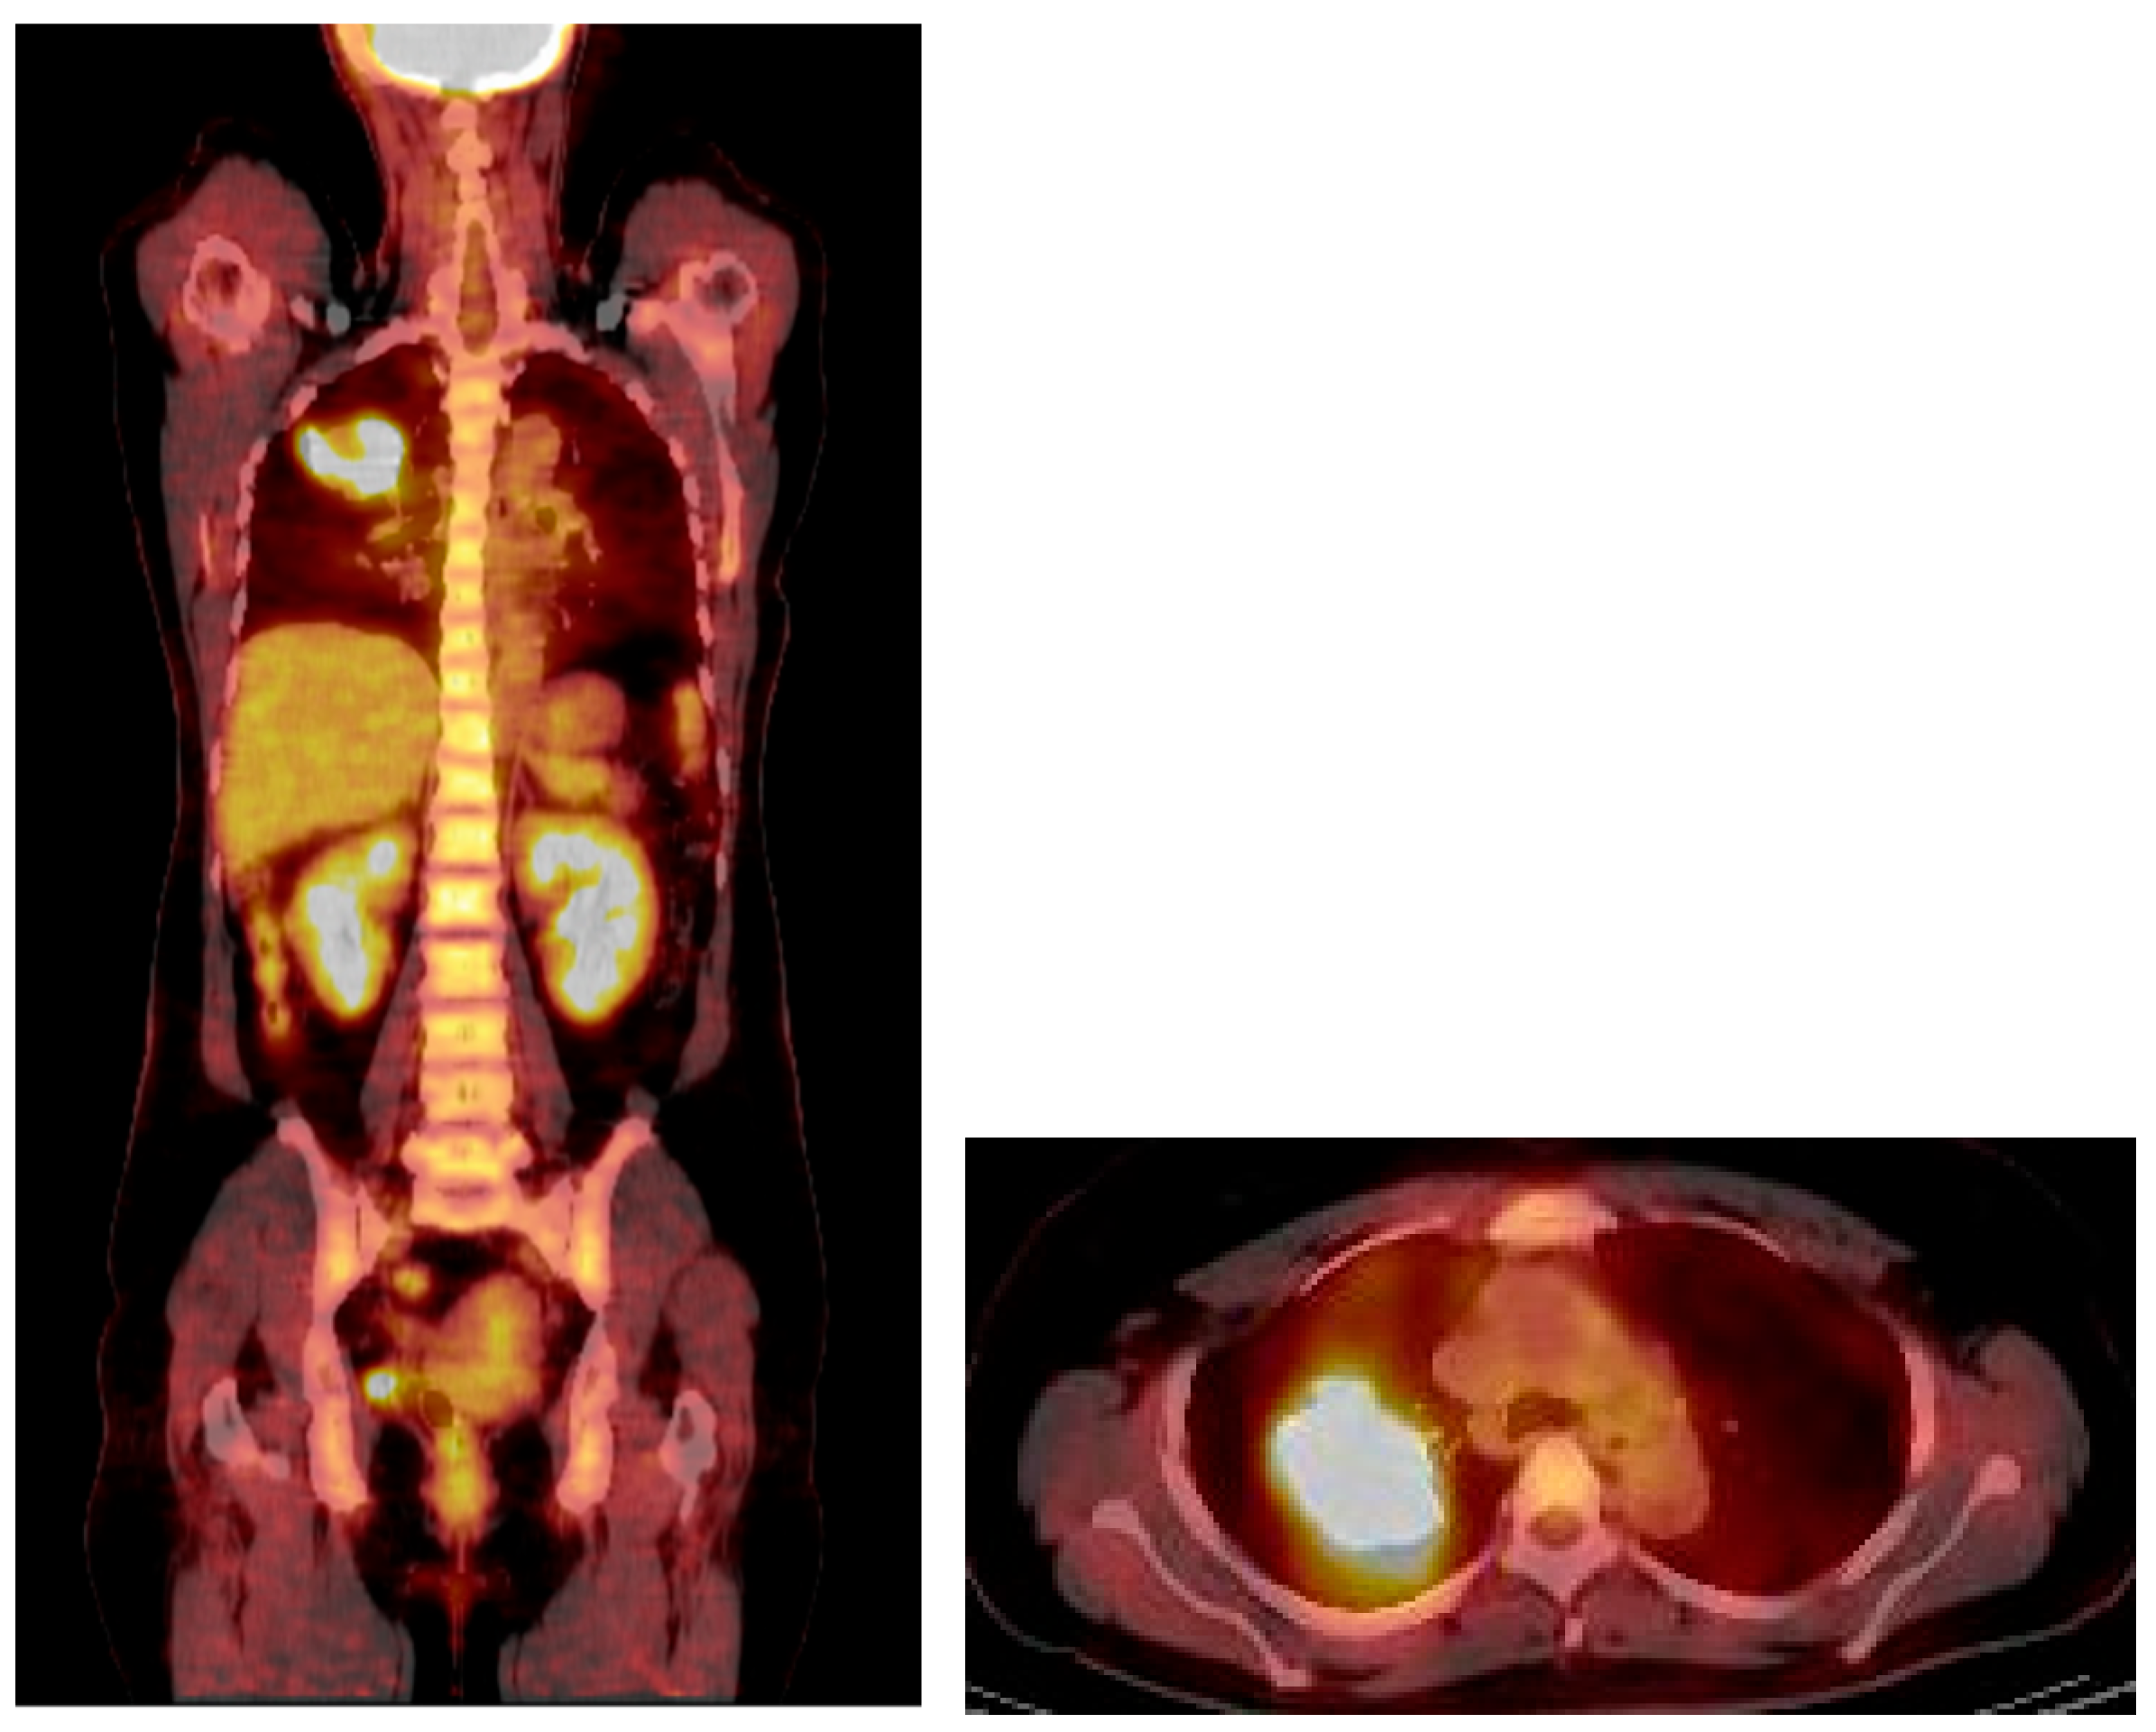

Figure 4.

PET/CT revealed intense FDG uptake in the corresponding mass in the right upper lung, with no evidence of extrathoracic involvement.

An F-18 FDG PET/CT torso scan was performed four days after the initial CT examination to assess the metabolic activity of the mass. Surprisingly, PET/CT revealed intense FDG accumulation in the mass, with a maximal standardized uptake value (SUVmax) of 13.4, and no other abnormal lesions were detected throughout the body (Figure 4). Since the brain was not included in PET/CT, brain MRI was performed three days after the PET scan. There were no particular abnormalities on the brain MRI.

Most intrathoracic SFTs show low-to-moderate FDG uptake in the mass on PET/CT. However, the tumor in this case exhibited high cellularity, which was suspected to have contributed to the high uptake of FDG. Although some studies have suggested that PET is not useful for differentiating between benign and malignant SFTs, avid uptake is interpreted as malignant potential.